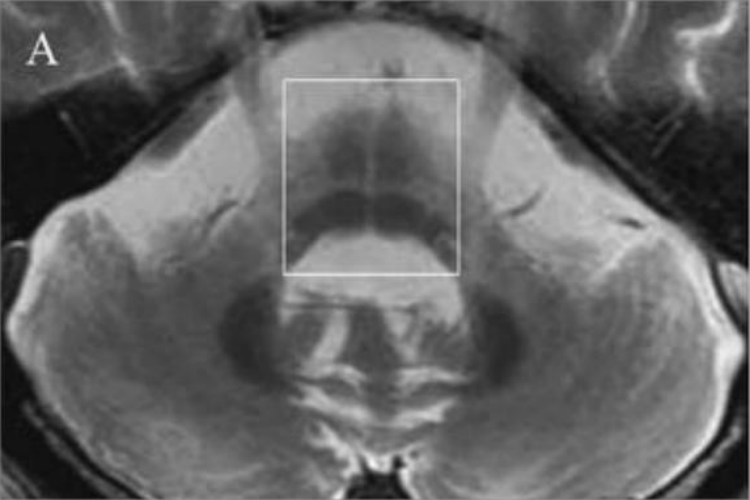

多系统萎缩病变累及脑桥、橄榄、小脑及自主神经系统,MRI显示壳核、小脑中脚、脑桥或小脑出现萎缩,第四脑室脑桥小脑脚池扩大;高场强(1.5T以上)MRI T2相可见壳核背外侧缘条带状弧形高信号、脑桥基底部“十字征”和小脑中脚高信号。患者可出现直立性低血压和排尿、排便异常,还可表现为帕金森症状(行动缓慢、动作僵硬等)和小脑性共济失调(动作笨拙、易失去平衡等)。